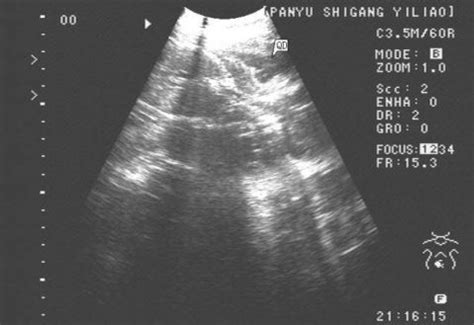

孕妇彩超诊断报告单上的两个图怎么看?

你好,孕妇彩超一般在怀孕期间定期做这方面的检查即可。各项指标需要找专业医生查看。一般情况下没有其他不适感或异常状况。做好孕期保健护理即可